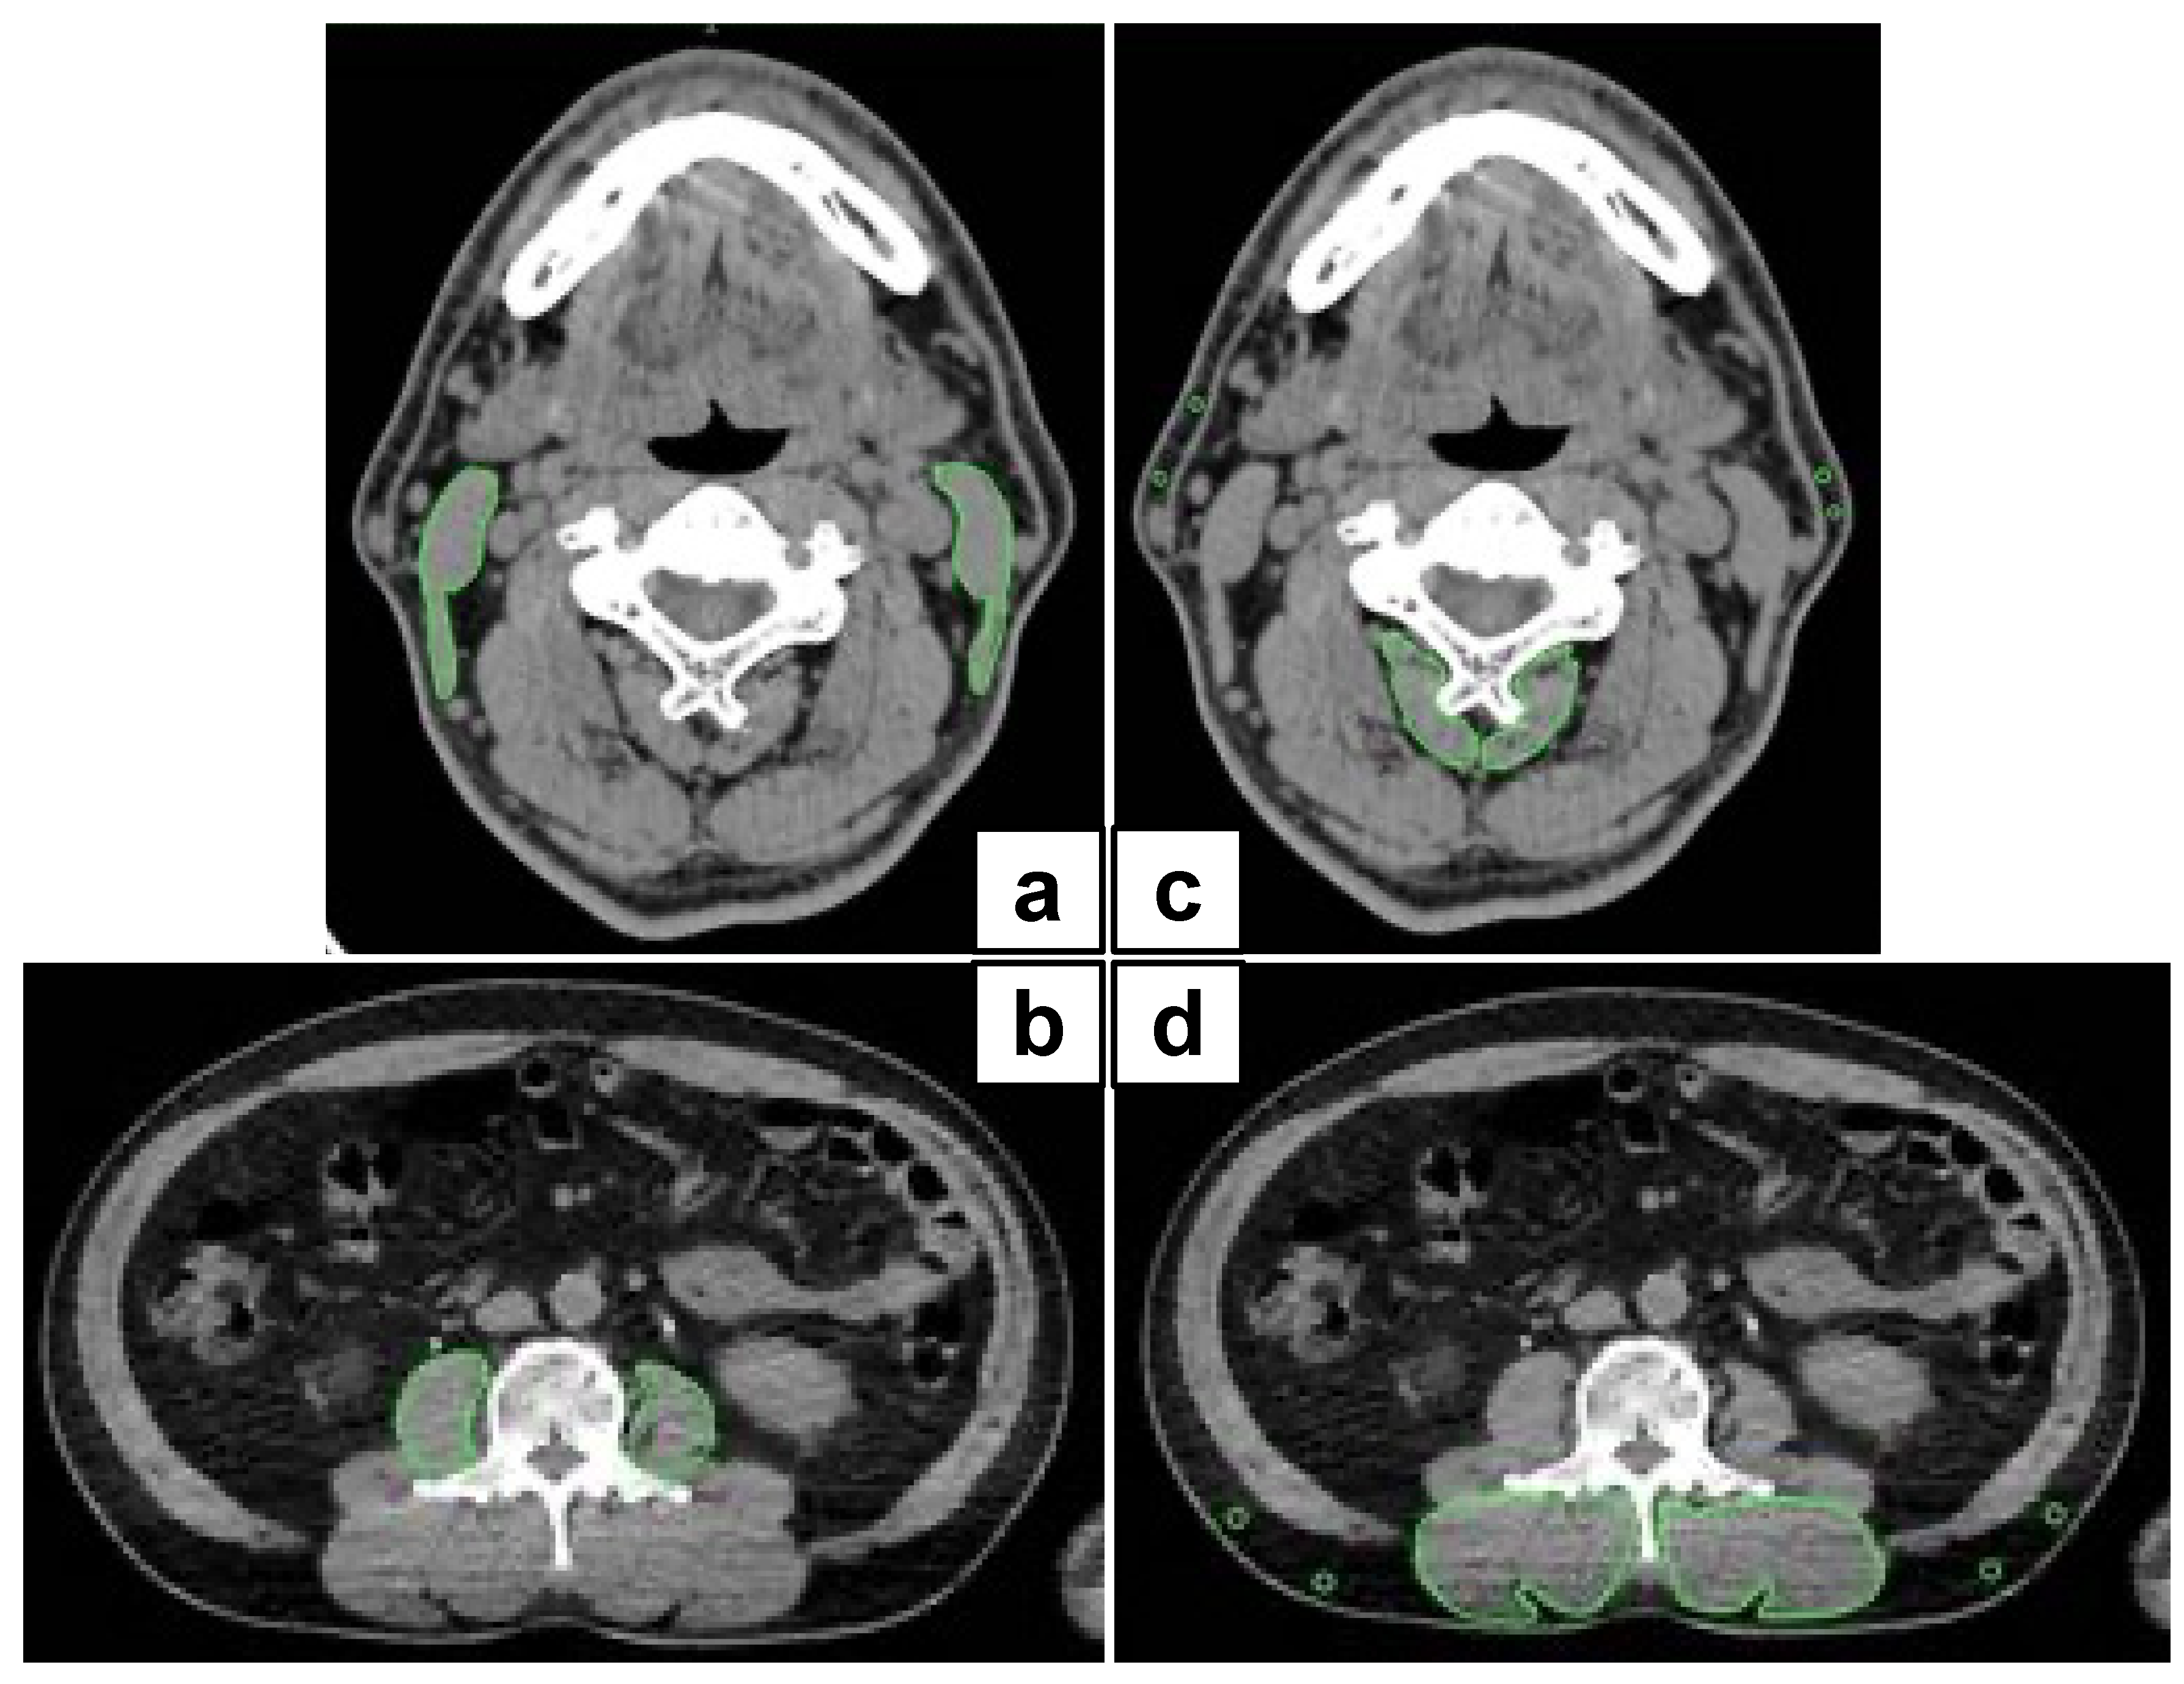

We employed the CT component of FDG PET/CT images as a single measure of whole-body imaging to detect primary squamous cell carcinoma within two weeks before surgery. Image analysis was performed according to a previous study [14] with slight modifications. Briefly, the area of skeletal muscle was determined as areas of −29 to 150 HU. Visceral and subcutaneous adipose tissue areas were determined as areas of −150 to −50 HU. Using OsiriX v.4.0 (Pixmeo SARL, Geneva, Switzerland), we evaluated the cross-sectional areas (cm2) of skeletal muscle in the third cervical vertebra (C3) and the L3 region and CT values (in Hounsfield units). Sternocleidomastoid muscle mass index (SCMI) and psoas muscle mass index (PMI) were determined by normalizing the cross-sectional areas for height (cm2/m2) (Figure 1a,b). Processus spinosus muscle—intramuscular adipose tissue content (P-IMAC) and intramuscular adipose tissue content (IMAC) were determined as the region of interest (ROI) of the multifidus muscle (Hounsfield units)/ROI of subcutaneous fat (Hounsfield units). CT values of four circular ROIs on the subcutaneous fat away from the major blood vessels were measured, and the average value was employed as the ROI of the subcutaneous fat (Figure 1c,d).

Figure 1.

Representative cross-sectional CT images at the C3 and L3 level. (a,b) We precisely traced the subfascial outline of the multifidus and sternocleidomastoid muscles. The SCMI and PMI were determined by normalizing the cross-sectional areas to height (cm2/m2); (c,d) P-IMAC and IMAC were measured by dividing the CT values of bilateral multifidus muscles at the C3 and L3 levels by the CT attenuation values of subcutaneous fat, respectively. CT, computed tomography; SCMI, sternocleidomastoid muscle mass index; PMI, psoas muscle index; P-IMAC, processus spinosus muscle—intramuscular adipose tissue content; IMAC, intramuscular adipose tissue content.